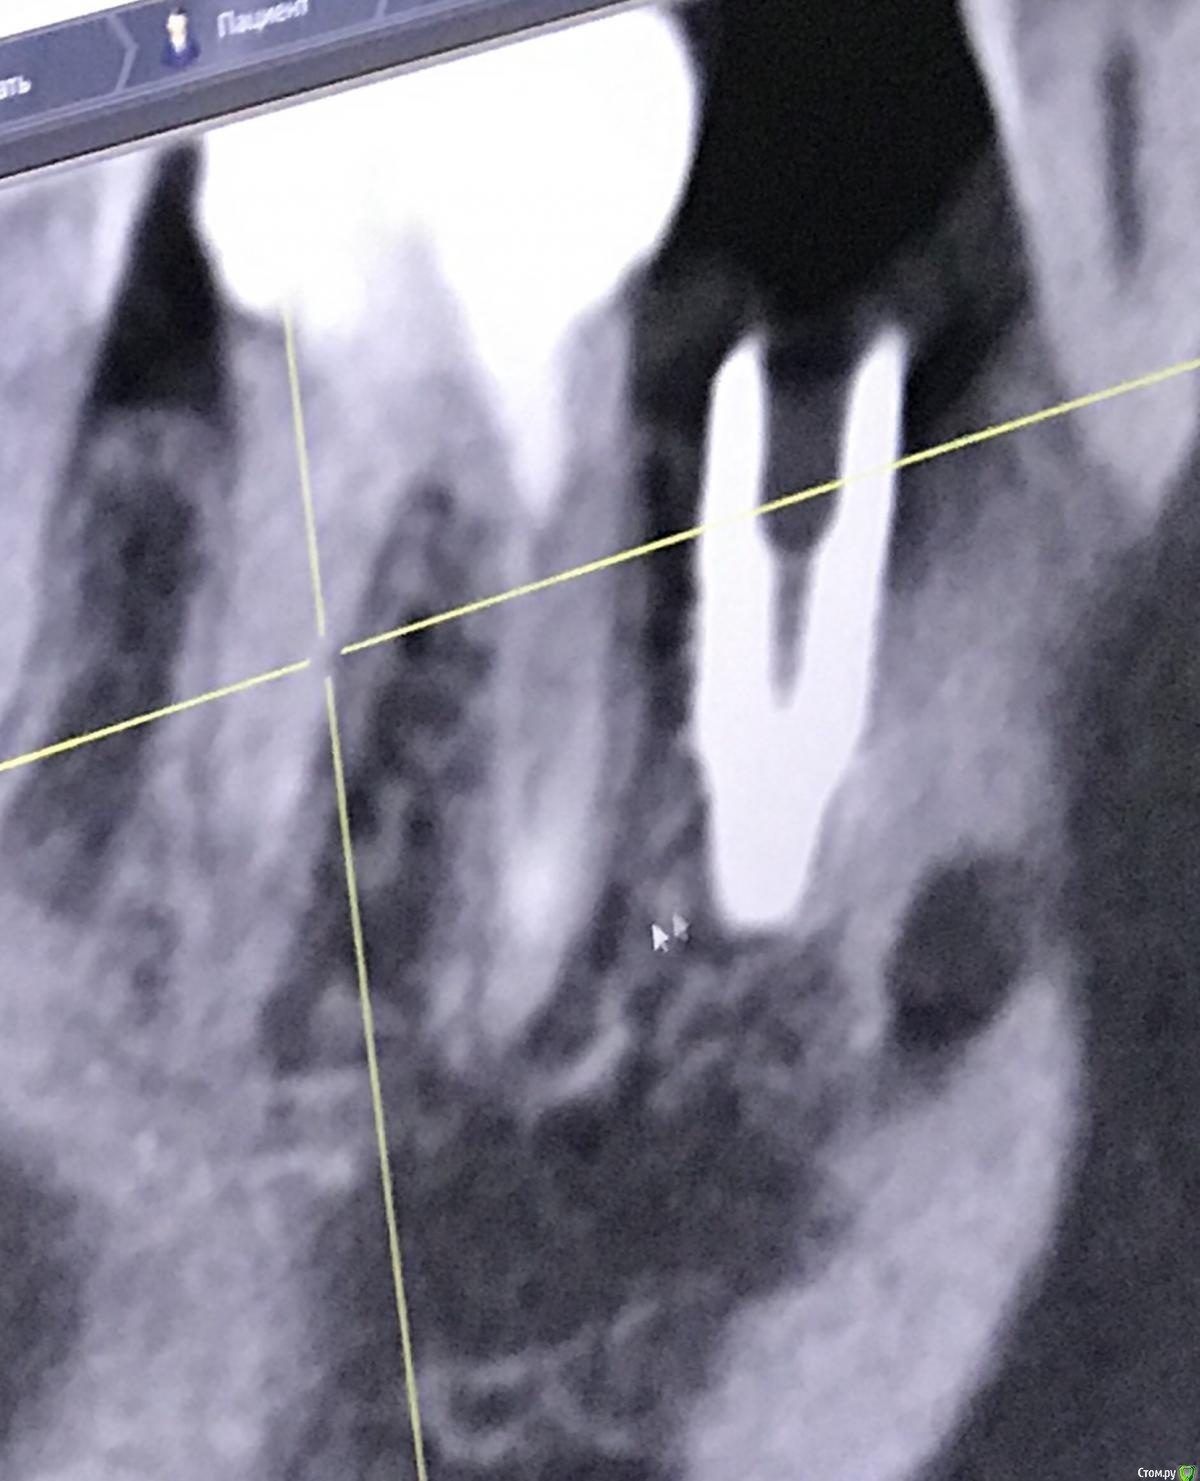

111 Опубликовано 25 декабря, 2020 Поделиться Опубликовано 25 декабря, 2020 Здравствуйте, уважаемые доктора,Посмотрите, пожалуйста, снимки и дайте Ваше видение ситуации.Субъективно - иногда с пульсацией побаливает область между 45 и 46. Но не часто совсем. Сам по себе 46 никаких ощущений не вызывает, был пролечен под микроскопом. Ортопедию не делали из-за наблюдения за 45. Ссылка на комментарий

111 Опубликовано 26 декабря, 2020 Автор Поделиться Опубликовано 26 декабря, 2020 (изменено) Iroil, спасибо большое за ответ.46 был кариес но не болел, периодонтита не было, никаких воспалений на верхушках не было. То есть 46 просто пролечили - обработали каналы, заложили кальций, и тд. Делалось под микроскопом, доктор очень хороший. По поводу 45 - изначально кости было достаточно по высоте, по объему пришлось подсыпать gen-oss 0,5 в момент имплантации, плюс сст с бугра. Вообще всё было хорошо, особо сильно не болело, без отёка зажило. В момент снятия швов - обнаружилась убыль кости в области 46, слегка оголился корень ближайший к 45, но мы как-то это не обсуждали с доктором. Установили Фдм, все ок.И вот пришло время ортопедии - это было летом 2019 - ортопед не захотел работать с имплантом, у которого на снимке оголена шейка. Десны достаточно при этом. Имплант не запротезирован.Спустя пару дней на визите у хирурга - я прошу выкрутить 45, мне отказывают, принято решение либо оставить как есть, либо подсыпать кости немного.Сейчас, декабрь 2020, я хожу с фдм и уже точно понимаю, что надо переустановить 45, но хирург предлагает 2 варианта:- оставить как есть и делать ортопедию (т.к. десна хорошая);- удалить 45 и 46 для создания удобного рабочего поля и имплантация 45, 46.Вот я пытаюсь понять, нельзя ли просто 45 выкрутить? Аккуратно удалить 45 не получится? (Очень не хочется расставаться с 46, сам по себе он не болит при накусывании и постукивании). Изменено 26 декабря, 2020 пользователем 111 Ссылка на комментарий